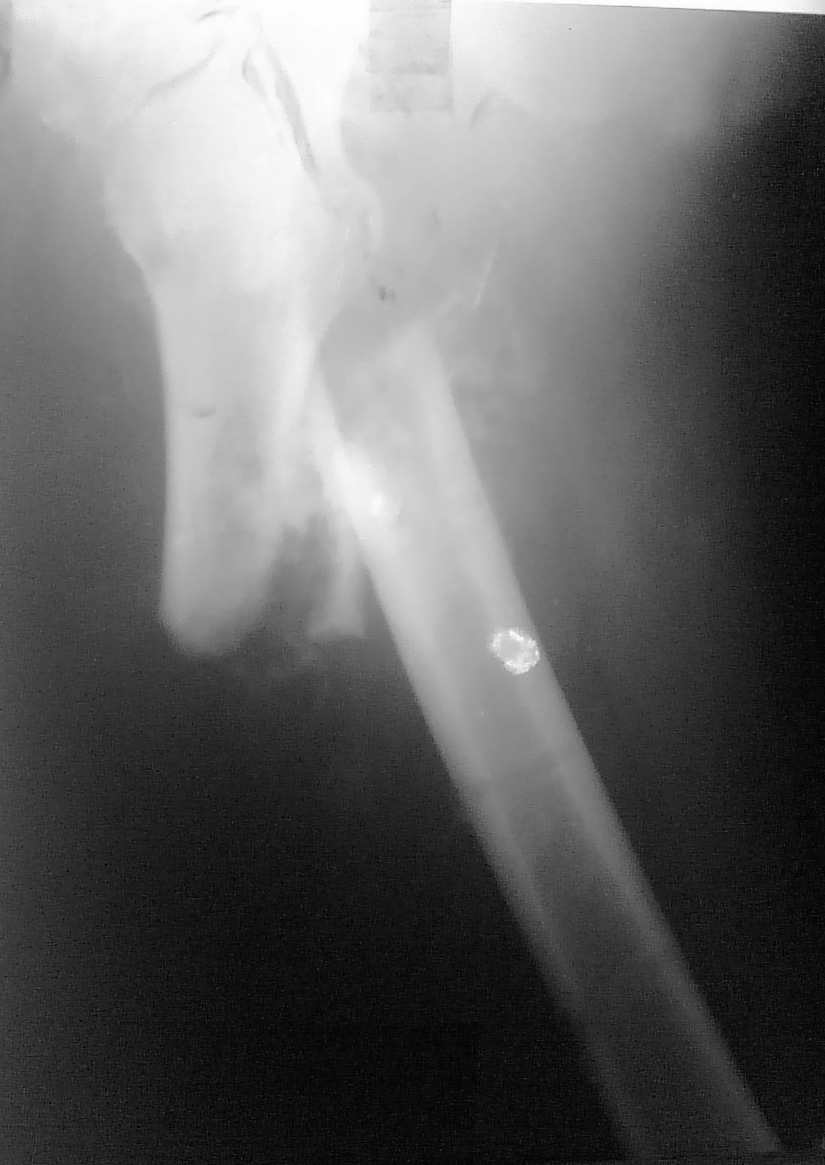

Консолидирующийся перелом бедренной кости

Больной Р. 28 лет поступил 14 12 09 с изолированным переломом бедренной кости в в/3

- наложена ССВ,в течении 12 часов развилась острая смешанная форма жировой эмболии произведена фиксация стержневым АВФ, ИТ в ОРИТ до 24 01 10, на данный момент больной в отделении травматологии, фиксирован ССВ имеем такую рентгенологическую картину, умеренный шат в зоне перелома, грубые психические нарушения, лабораторные показатели нормализовались, раны зажили.

Вопросы относительно фиксации и репозиции:

1 возможен ли И-медуллярный МОС (учитывая перенесенную тяжелую форму ЖЭ)? на данный момент отдаем предпочтение накостному МОСу

2 Собрали, согласно руководства, спицевой аппарат предложенный А. Н. Челноковым и соавт.для дозированной длительной дистракции (наш первый опыт) соответственно имеем только теоретические представления о его использовании и интересуют нюансы и особенности. Какие "сюрпризы" возможны в конкретном случае,возможна ли дистракция не вмешиваясь в зону перелома?